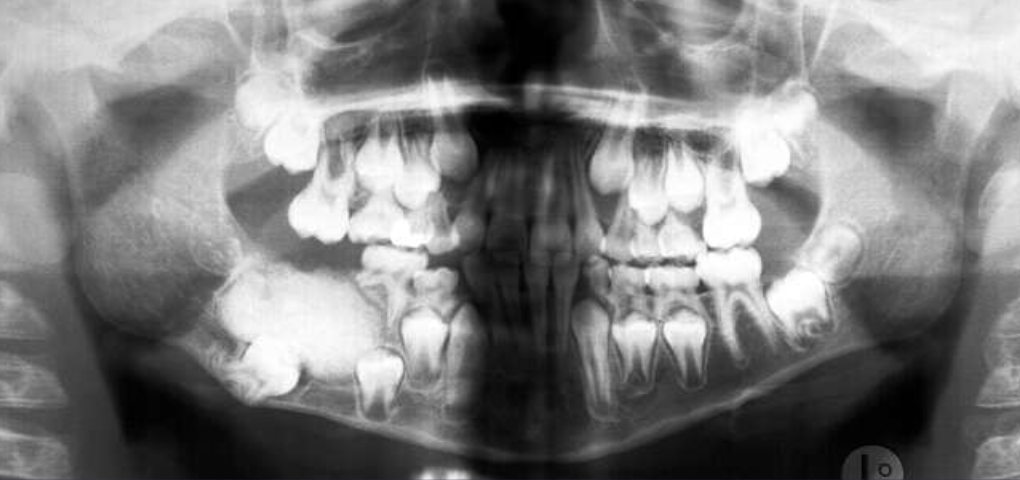

radiographic features of cherubism

bilateral multilocular radiolucencies

multicystic appearance

expansion/thinning of cortices

uncommon perforation

tooth displacement, resorption